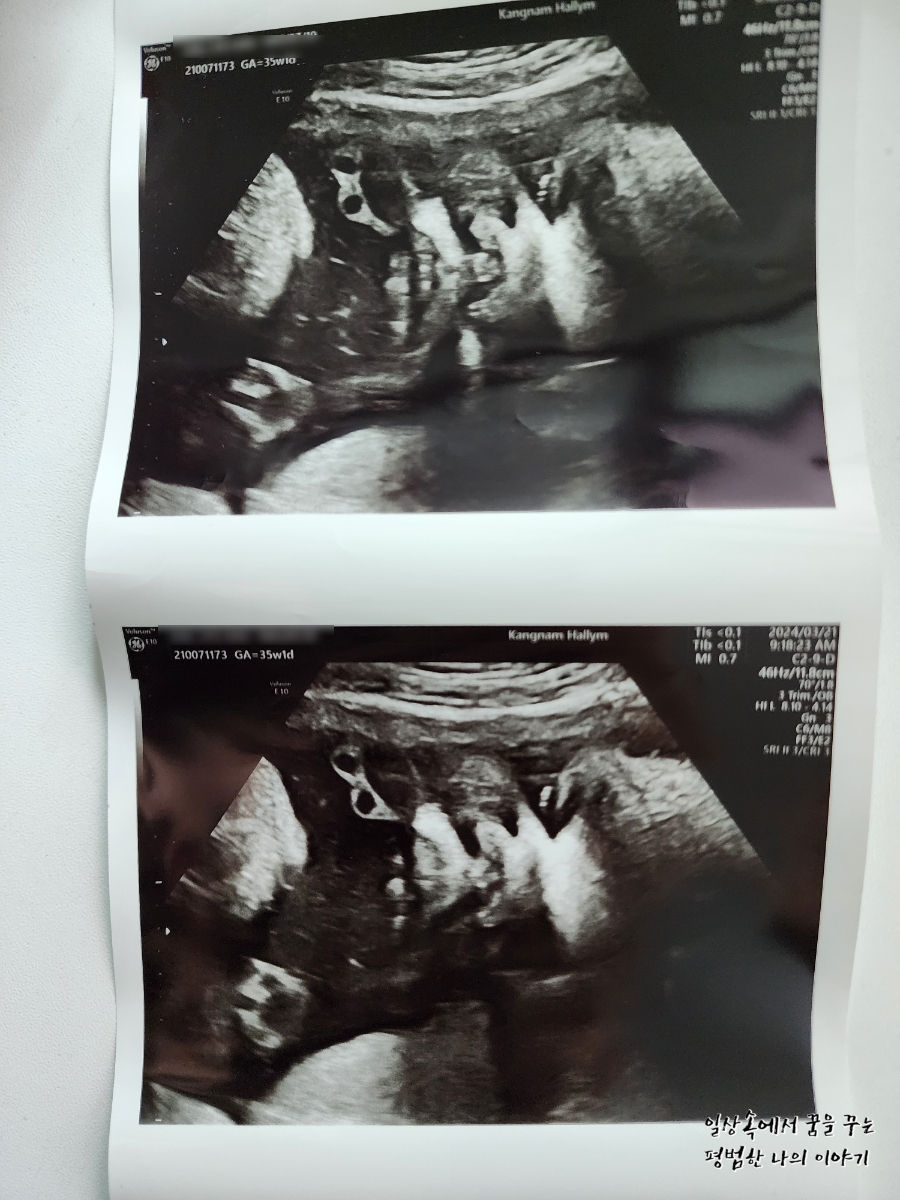

3주 만에 방문한 병원에서 딸내미는 더욱 커져서 35주 차에 첫째 37주 차 때 사이즈와 모든 게 비슷해져 있었다.(머리둘레, 배 둘레, 몸무게 등) 첫째를 꽉 채운 40주 차에 유도 분만으로 출산했는데 4.09kg으로 무척 커서 출산하고 의료진과 함께 놀랐던 기억이 있다. 둘째는 이를 훨씬 앞서고 있으니 의사 선생님도 40주까지 기다리는 건 무리가 있다고 생각하시는 것 같다. 나는 38주 차에 유도 분만을 하고 싶으나 의사 선생님은 39주까지 채우고 유도 분만 하기를 권하셨다. 우선 나의 몸이 아무런 준비가 되지 않았기 때문에 유도 분만이 실패할 가능성이 있어 38주보다는 39주 차를 더 선호하시는 것 같다. 나는 첫째가 4.09kg으로 태어난 탓에 우량아라 인큐베이터에 일주일이나 있었던 게 싫었던지라 이번에는 어떻게든 4kg 미만으로 아이를 출산하여 나와 함께 퇴원하고 싶은 마음이 크다. 그러면서도 최대한 유도 분만을 하고 싶고 제왕절개로 상황이 흘러가게 되는 건 또 싫어 고민이 많다. 여태까지 나의 몸무게는 9kg 정도 늘었는데 첫째 때보다는 양호한 수준이다. 그래도 또 알 수가 없는 게 막달에 일주일에 1~2kg은 쉽게 몸무게가 늘기 때문에 첫째 때만큼 살이 찐 상태에서 출산할 가능성도 없지 않다.